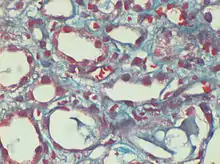

Dilated peri-tubular capillaries filled with sickled RBCs, original Gomori's trichrome stain, × 400.[1]